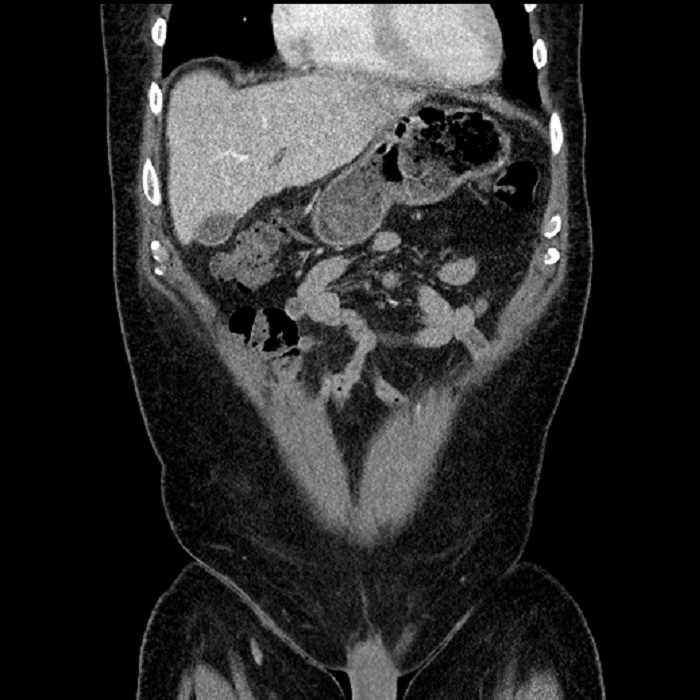

• Large fluid density structure in hepatic segments 7 and 8 measuring 10 x 7 x 7 cm with internal septation and circumferential ill-defined low density compatible with edema

• Peripherally enhancing subcapsular collections along the anterior margin of the left hepatic lobe measuring 3 x 1 cm and 2 x 1 cm

• Mild mural thickening of a segment of the sigmoid colon with adjacent fat stranding and a 1.5 cm fluid and gas collection along the tip of an inflamed diverticulum

• Loss of the normal fat plane between this collection and adjacent loops of small bowel, which demonstrate mural thickening

• High grade stenosis of the left common iliac artery, with the left internal and external iliac arteries remaining patent

Acute sigmoid diverticulitis complicated by a small contained perforation and a large abscess in the right hepatic lobe. Additional small subcapsular abscesses along the anterior margin of the left hepatic lobe.

Additionally, loss of the normal fat plane between the peridiverticular collection and adjacent thickened loops of small bowel raises the potential for an enterocolonic fistula.

High grade stenosis of the left common iliac artery. The left external and internal iliac arteries are patent.

Hepatic abscess showing the double target sign with low density internally surrounded by a thin inner enhancing rim (red arrow) and ill-defined outer low density rim (yellow arrow). Blue arrow indicates an internal septation. Red arrows: additional smaller subcapsular abscesses. Red arrow: focal contained perforation associated with diverticulitis.